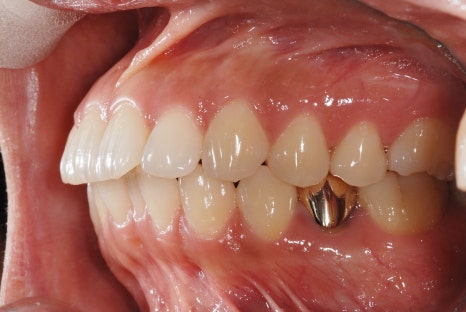

<Before-and-after orthodontic treatment photos>

Treatment period: 23.01.18 - 24.6.04 (about 1 year and 6 months)

Treatment performed: protrusion, midline improvement